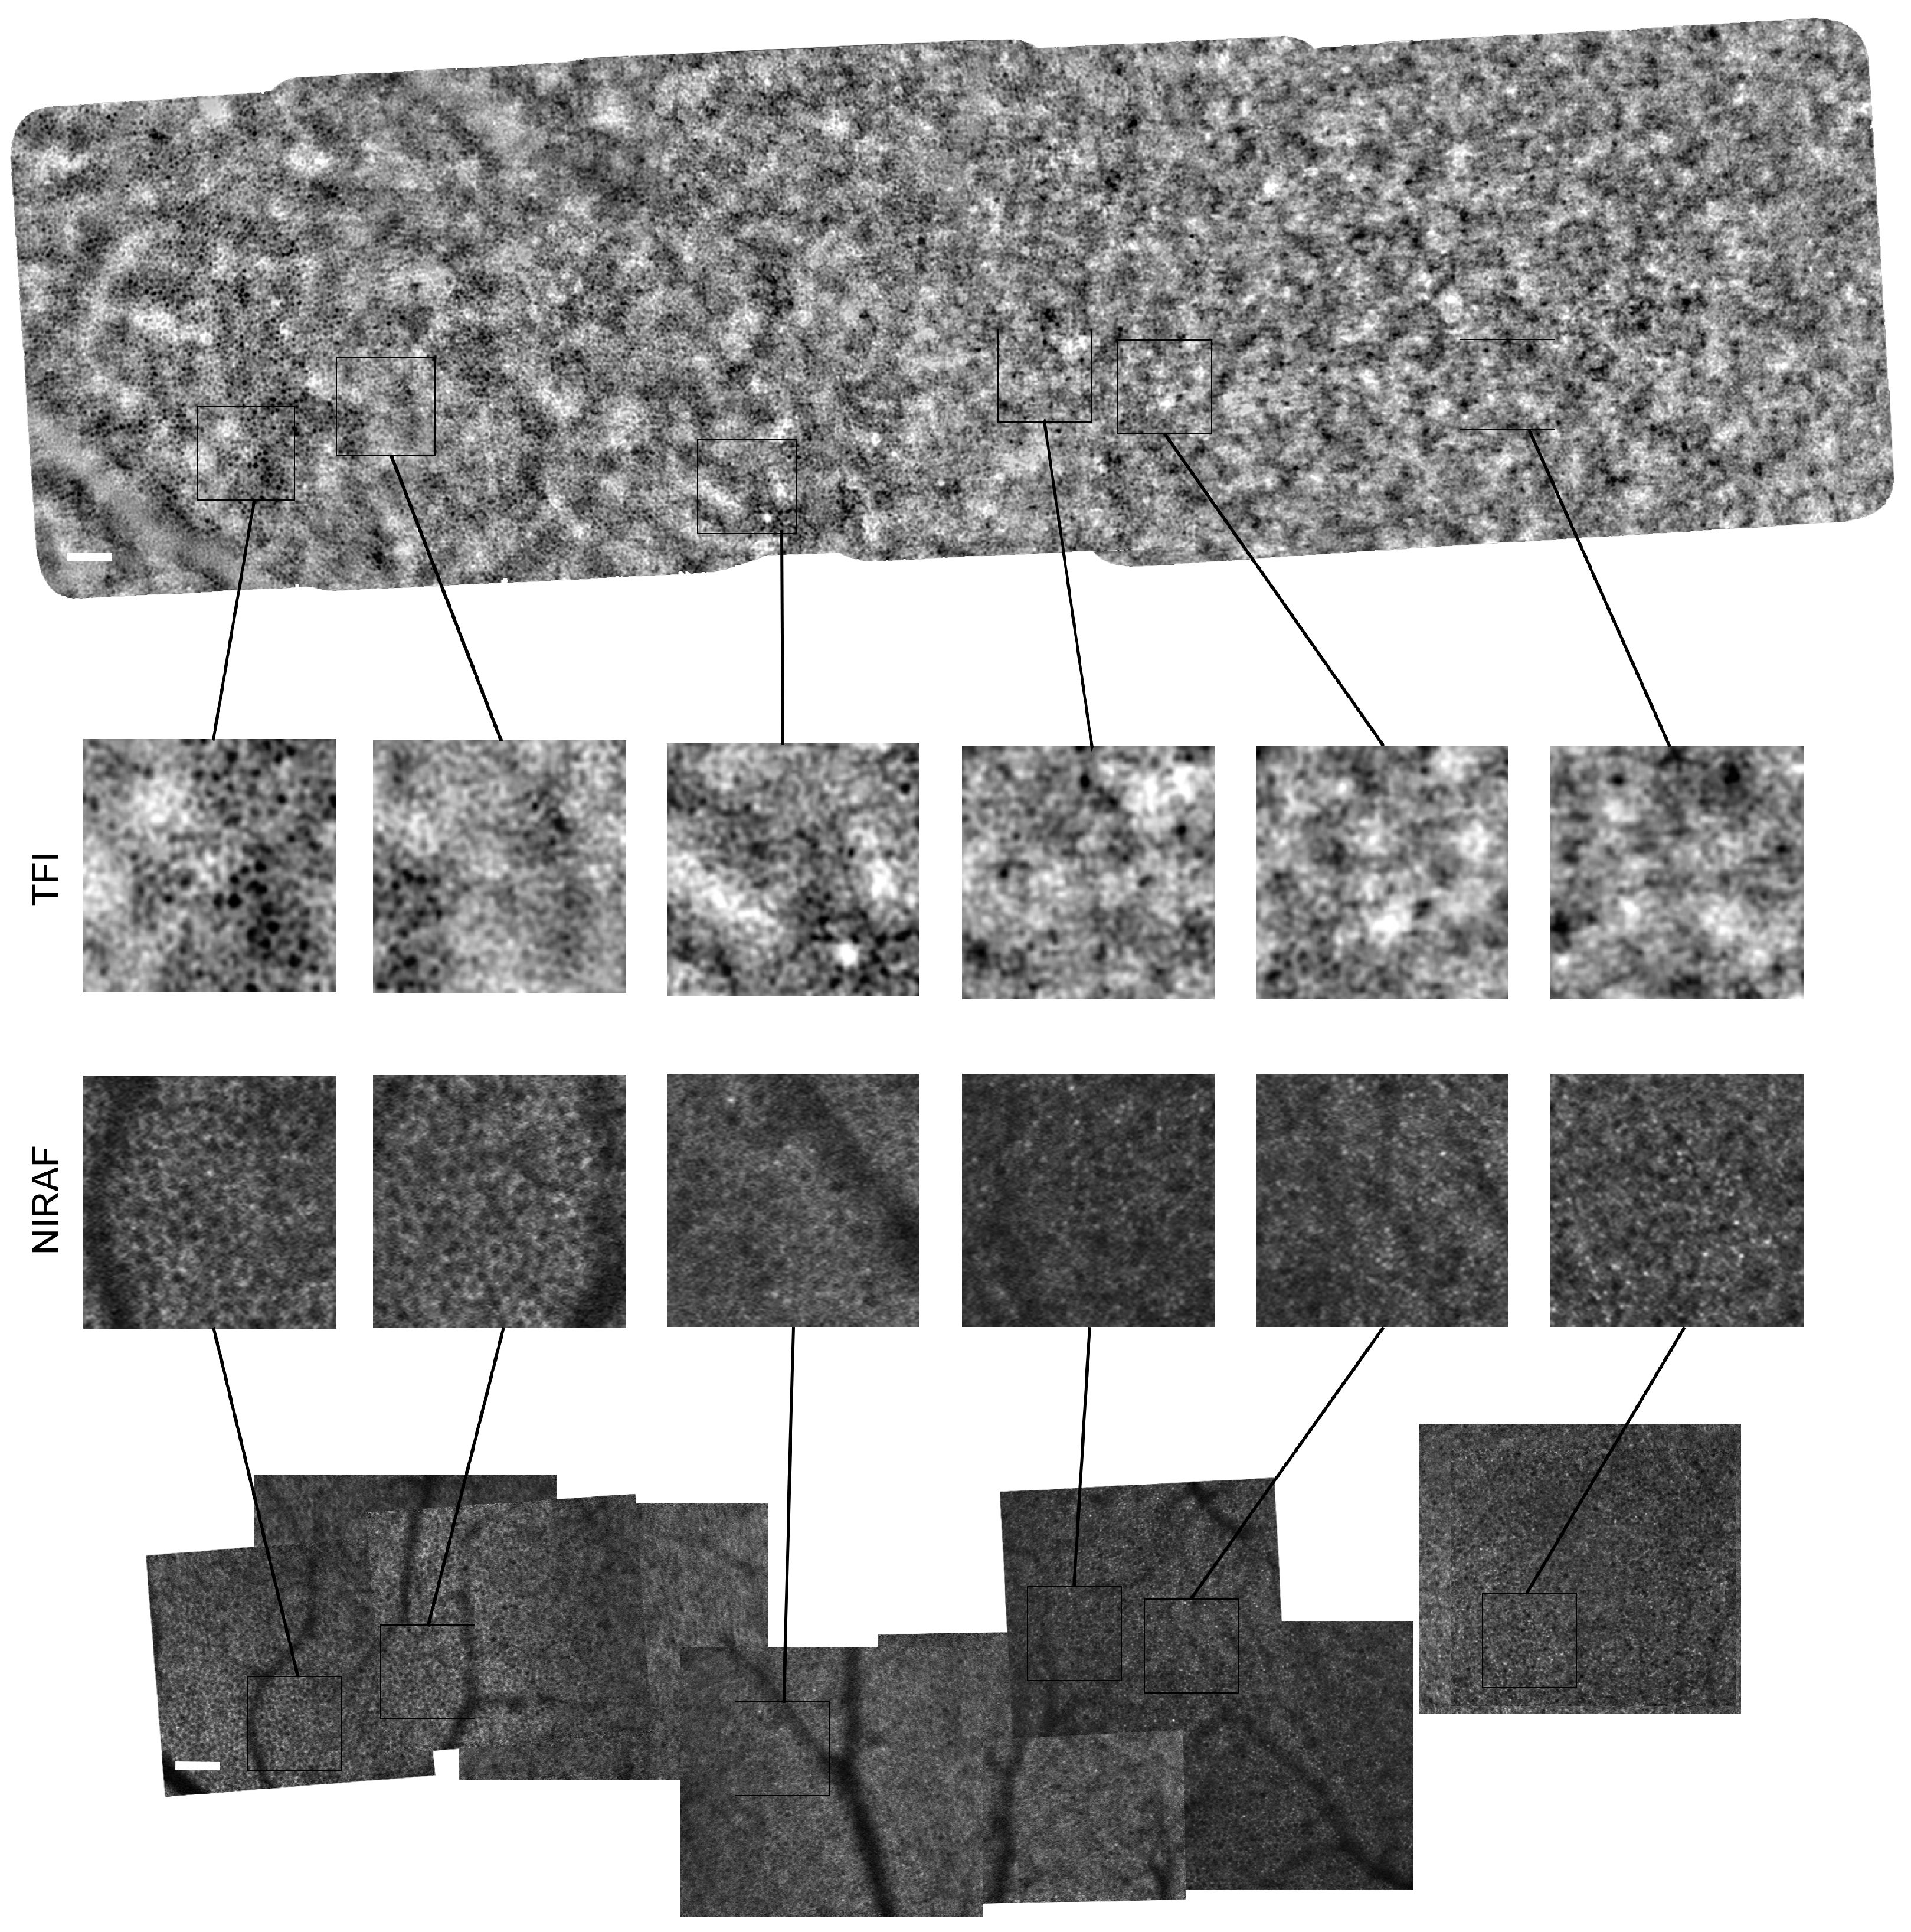

3.1. Images of TFI and NIRAF of Same Regions

Appendix A. Montages of TFI and NIRAF Images from Other Subjects

Appendix A.1. Montages of Subject #2

Appendix A.2. Montages of Subject #3